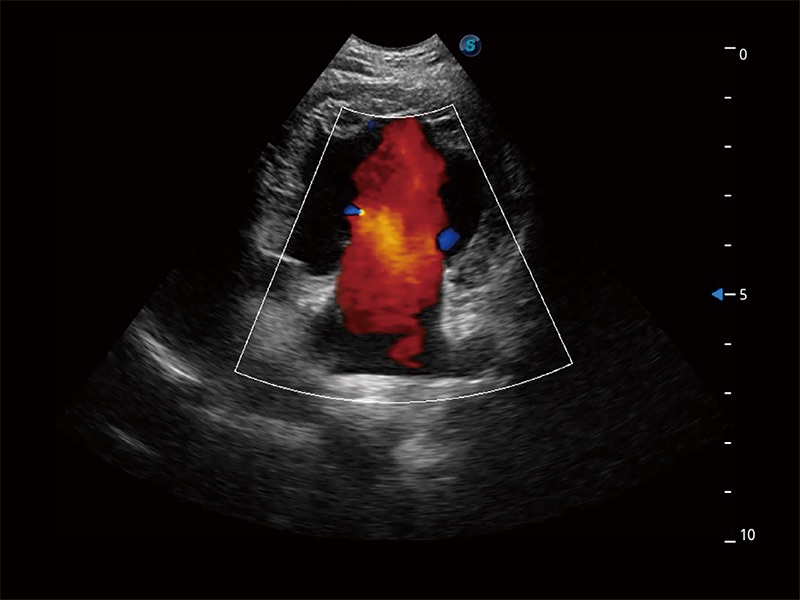

在傳統(tǒng)二維血流成像的基礎(chǔ)上,呈現(xiàn)血流的立體感,具有動感的生命力之美。即便是微小的血管也能輕松應(yīng)對,提高了血流的視覺敏感性。